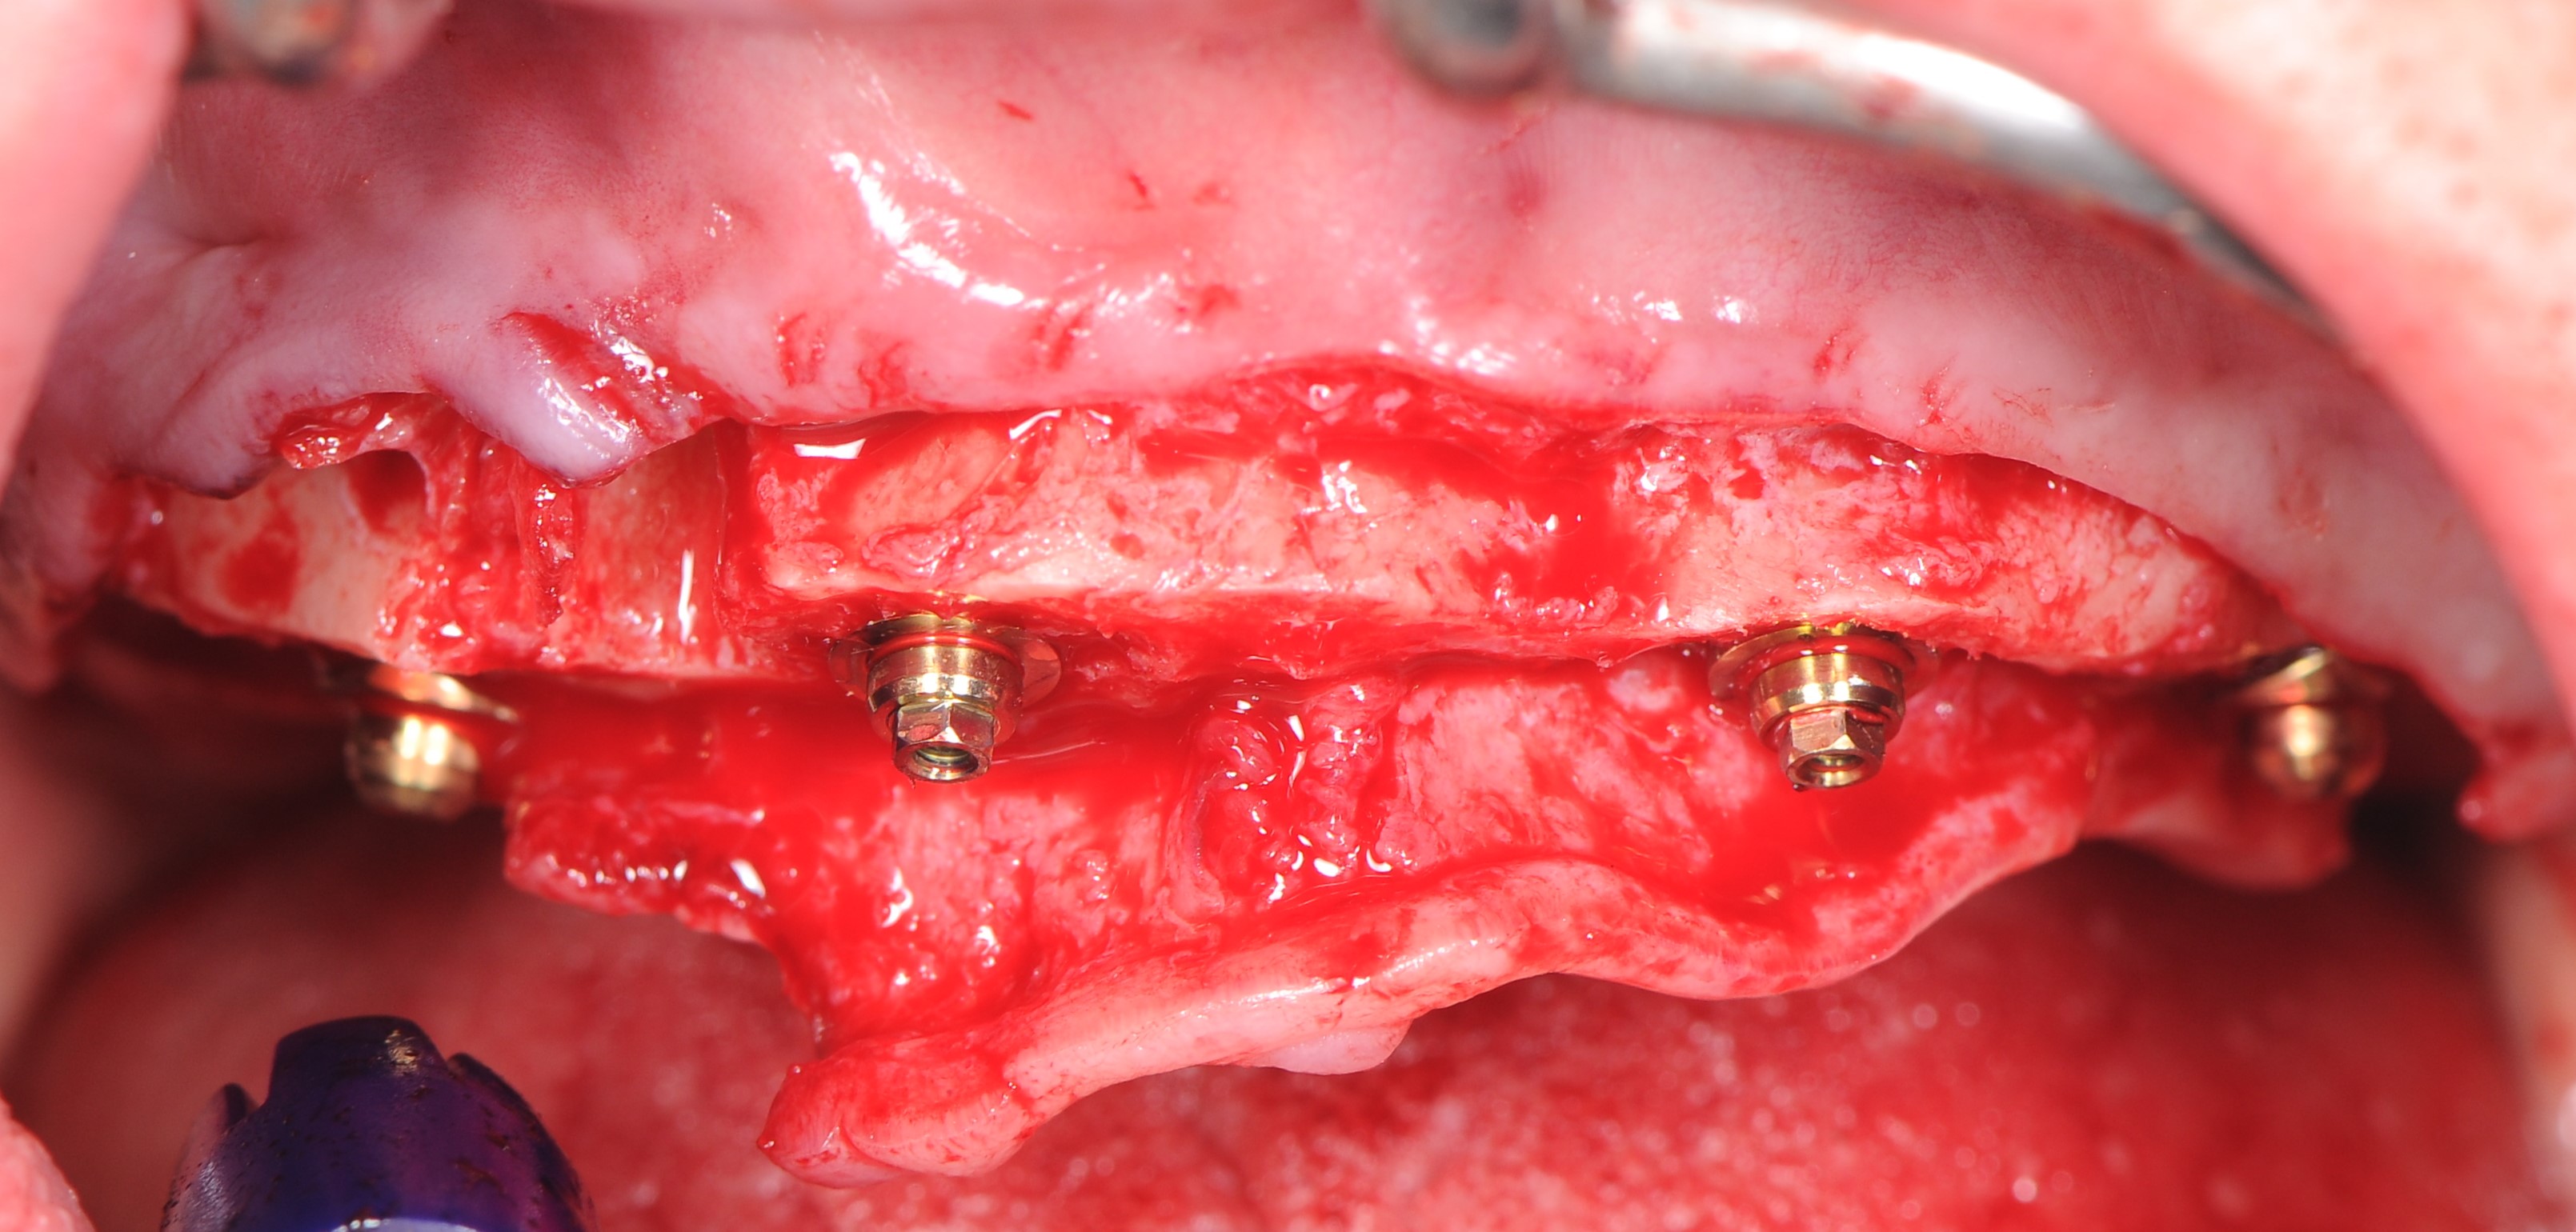

Лунка удаленного 1.3 зуба аугментирована костным фрагментом полученном при редукции альвеолярного гребня. Его клиновидная форма позволила провести фиксацию в лунке без использования дополнительных материалов: титановых винтов или пластин. Поднутрения в окружности костного фрагмента были заполнены костно-пластическим материалом «OsteoBiol ® mp3». Области «Multi – unit» абатментов и зоны костной аугментации дополнительно изолированы коллагеновыми мембранами Creos Xenoprotect. (рис. 22-25).

На «Multi – unit» абатменты зафиксированы пластиковые заживляющие колпачки. В небной части слизисто-надкостничного лоскута было сделано 2 перфорационных разреза в проекции фронтальных имплантатов, лоскут ротирован в вестибулярном направлении с расположением колпачков в зонах перфорации. Рана ушита шелковыми нитями без натяжения (рис 26,27,28).